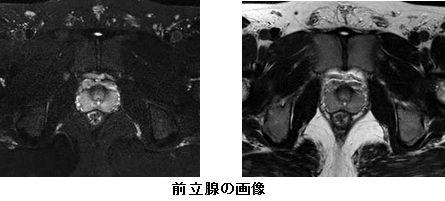

腹部のMRI MRI of the thoracic and the lumbar spine. A: sagittal T2の詳細情報

MRI of the thoracic and the lumbar spine. A: sagittal T2。116D52 | 卵巣腫瘍 国試 | テコプラ。腹部領域のMRI最新アプリケーション-技術解説 - 株式会社日立。Vertebral Compression Fracture - MRI Images - The Pain。「腹部のMRI」荒木 力定価: ¥ 13000#荒木力 #荒木_力 #本